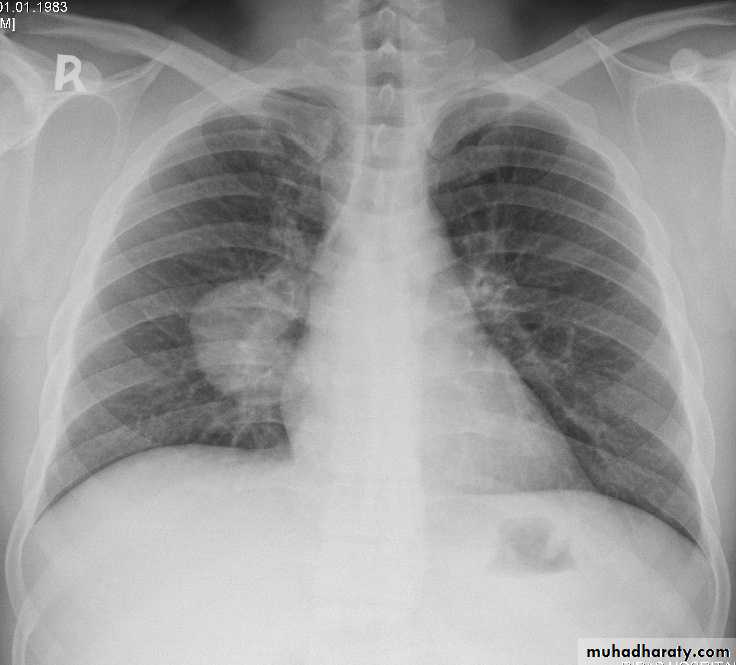

Lung cancer x ray

Pancoast Tumor